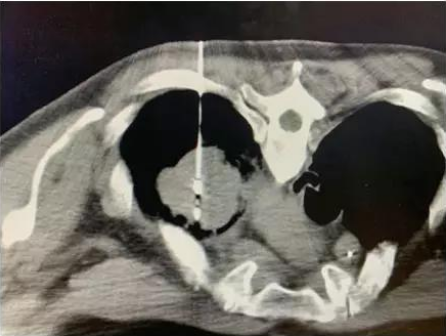

近日,广州复大肿瘤医院来了一位俄罗斯的老人家,患有肾癌肺转移,由于CT显示老人家的肿瘤血运非常丰富,任何治疗都可能引起大出血,危及生命,当地医院束手无策只好让他回家。

经CT检查发现肿瘤血运非常丰富易出血。所以复大的医生先给他做了一个穿刺活检,明确肿瘤的性质。